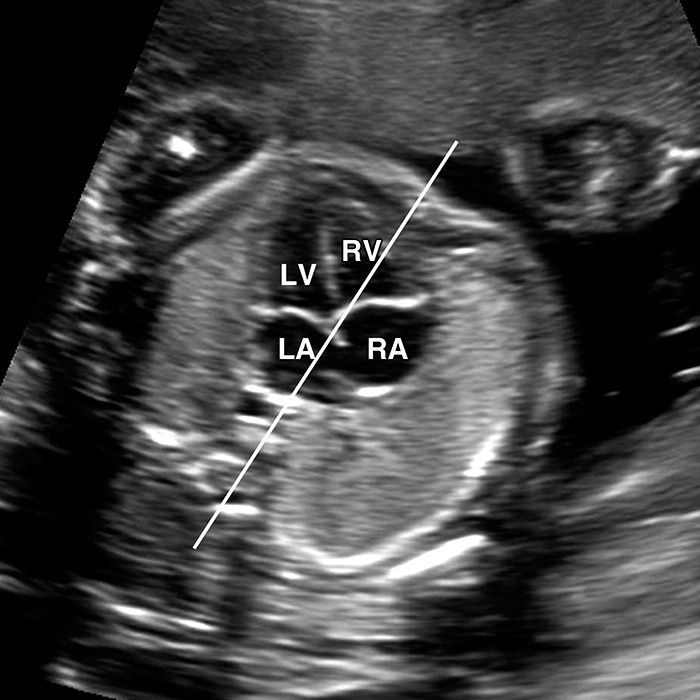

A fetal echocardiogram (fetal echo) uses sound waves to create pictures of an unborn baby's heart. This painless ultrasound exam shows the structure of the heart and how well it's

working. Doctors may order a fetal echo to look for any major problems with the developing baby's heart walls and valves, the blood vessels leading to and from the heart, and the

heart's pumping strength.

A fetal echocardiogram is done in a darkened room, while you are lying down. Gel put on your belly helps sounds waves travel from the echo transducer to the baby's heart and back.